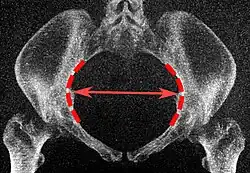

| Transverse diameter | Extends across the greatest width of the superior aperture, from the middle of the brim on one side to the same point on the opposite; | about 135 mm. |

Low-dose CT scan of the transverse diameter of the pelvic inlet, as part of pelvimetry -